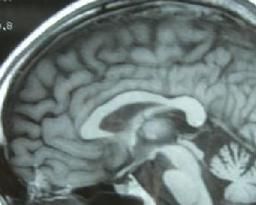

8. 影像學檢查 MRI發現殼核、橋腦、小腦中腳和小腦等有明顯萎縮,第四腦室、腦橋小腦腳池擴大。高場強(1.5T以上)MRI T2相可見殼核背外側緣條帶狀弧形高信號、腦橋基底部“十字征”和小腦中腳高信號。18F-脫氧葡萄糖PET顯示紋狀體或腦幹低代謝。